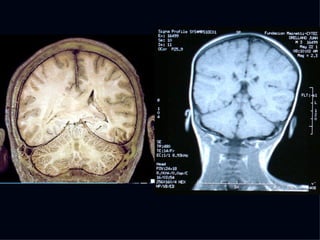

The document discusses the contributions of various figures in the field of medical imaging, including Wilhelm Röntgen and his discovery of X-rays, and the development of CT imaging and MRI technology. It highlights the historical significance of early imaging techniques and the initial skepticism from medical professionals regarding their usefulness. Key milestones in imaging are noted, along with the eventual acceptance of such technologies in clinical practice.